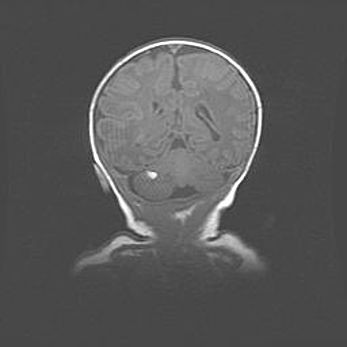

Подострая гематома правой гемисферы мозжечка.

Наружная гидроцефалия.

Возраст: 15 дней

Вес: 3100 г

Пол: женский

Окружность головы: 37 см

Срок гестации: 35-36 недель

При открытой наружной форме гидроцефалии у новорожденных расширяются и переполняются субарахноидные пространства.

Кровоизлияния в мозжечок имеют две клинико-анатомические формы: полушарные гематомы и кровоизлияния в червь.

К появлению этой патологии может привести: повреждения головного мозга, возникающие в результате асфиксии и гипоксии плода при беременности, или травмы во время родов. Редко гематома мозжечка может быть результатом первичной коагулопатии и сосудистой мальформации, диссеминированном внутрисосудистом свертывании, изоиммунной тромбоцитопении.